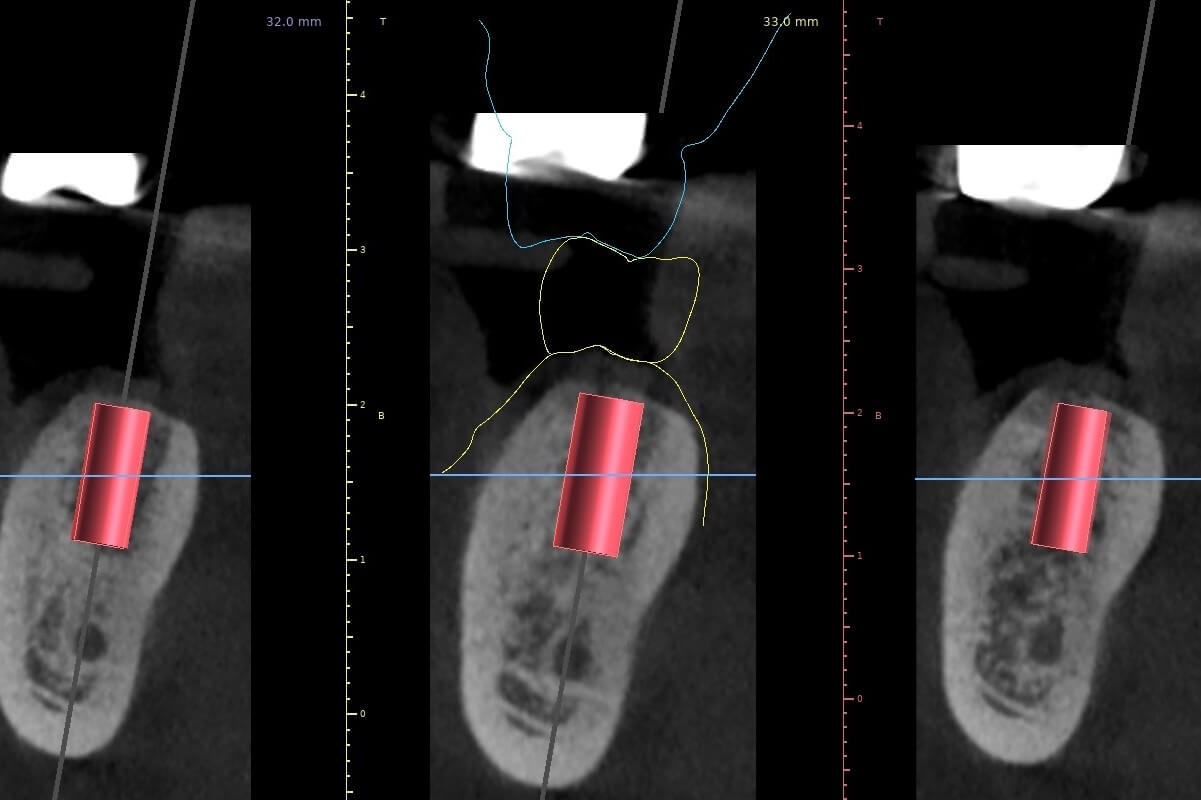

再來,透過電腦程式搭配 3D斷層掃描CT 的應用,可以準確地測量出齒槽骨立體的寬度與深度,以便找出最適當的植牙位置與角度。這些資訊也可判斷出植牙位置的骨頭條件是否足夠?如果需要補骨手術時,需要用何種的手術方式重建? 讓我們在手術之前就可以有一個精準的規劃。

依照電腦的規劃結果,可製做出需要的手術導引版和相關的植牙零件,使得手術結果與電腦模擬達到零誤差。